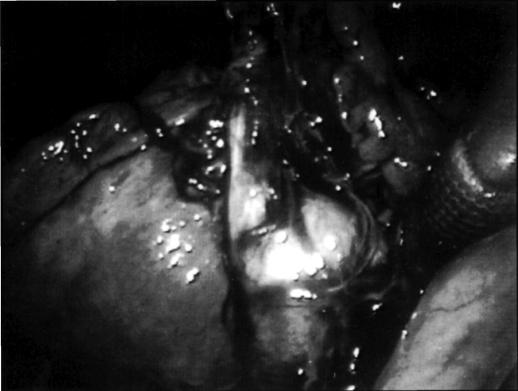

This is a report of a laparoscopic cholecystectomy in an 82-year-old white female with volvulus of the gallbladder presenting with a chief complaint of chest pain.

这是一例82岁白人女性因胆囊扭转以胸痛为主诉接受腹腔镜胆囊切除术的报告。